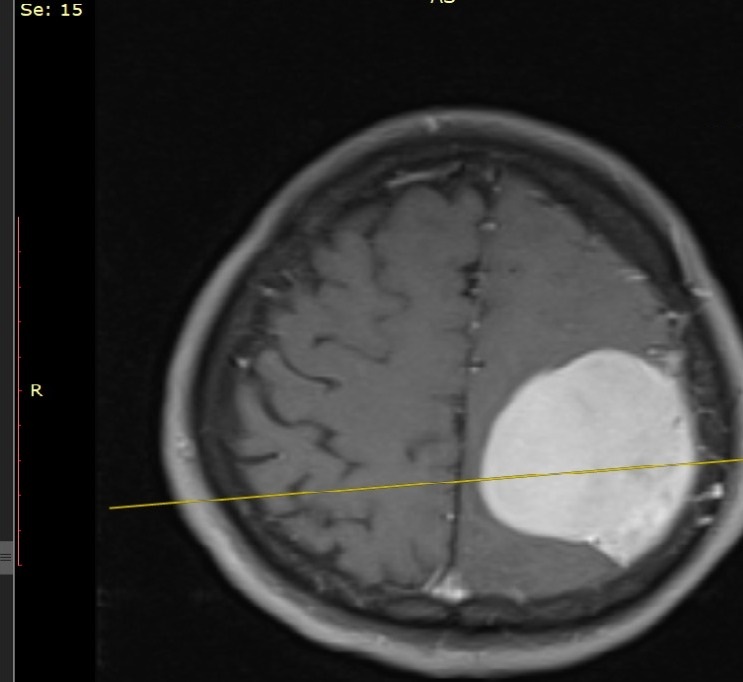

„Pacientul a fost internat ieri prin Unitatea de Primiri Urgențe, fiind diagnosticat cu o tumoră cerebrală gigantă care îi punea viața în pericol, prin comprimarea creierului. I s-au efectuat analize medicale, inclusiv testul pentru COVID-19. După studierea atentă a cazului am decis intervenția chirurgicală și am practicat rezecția completă a tumorii care a avut o mărime de 6/5 cm”, explică Șef Lucrări Dr. Vicențiu Săceleanu.

Intervenția chirurgicală a fost efectuată cu microscopul operator performant din dotarea secției și a durat aproximativ 4 ore. Operația a fost un succes și urmează ca pacientul să fie suspus unor controale post operatorii amănunțite.